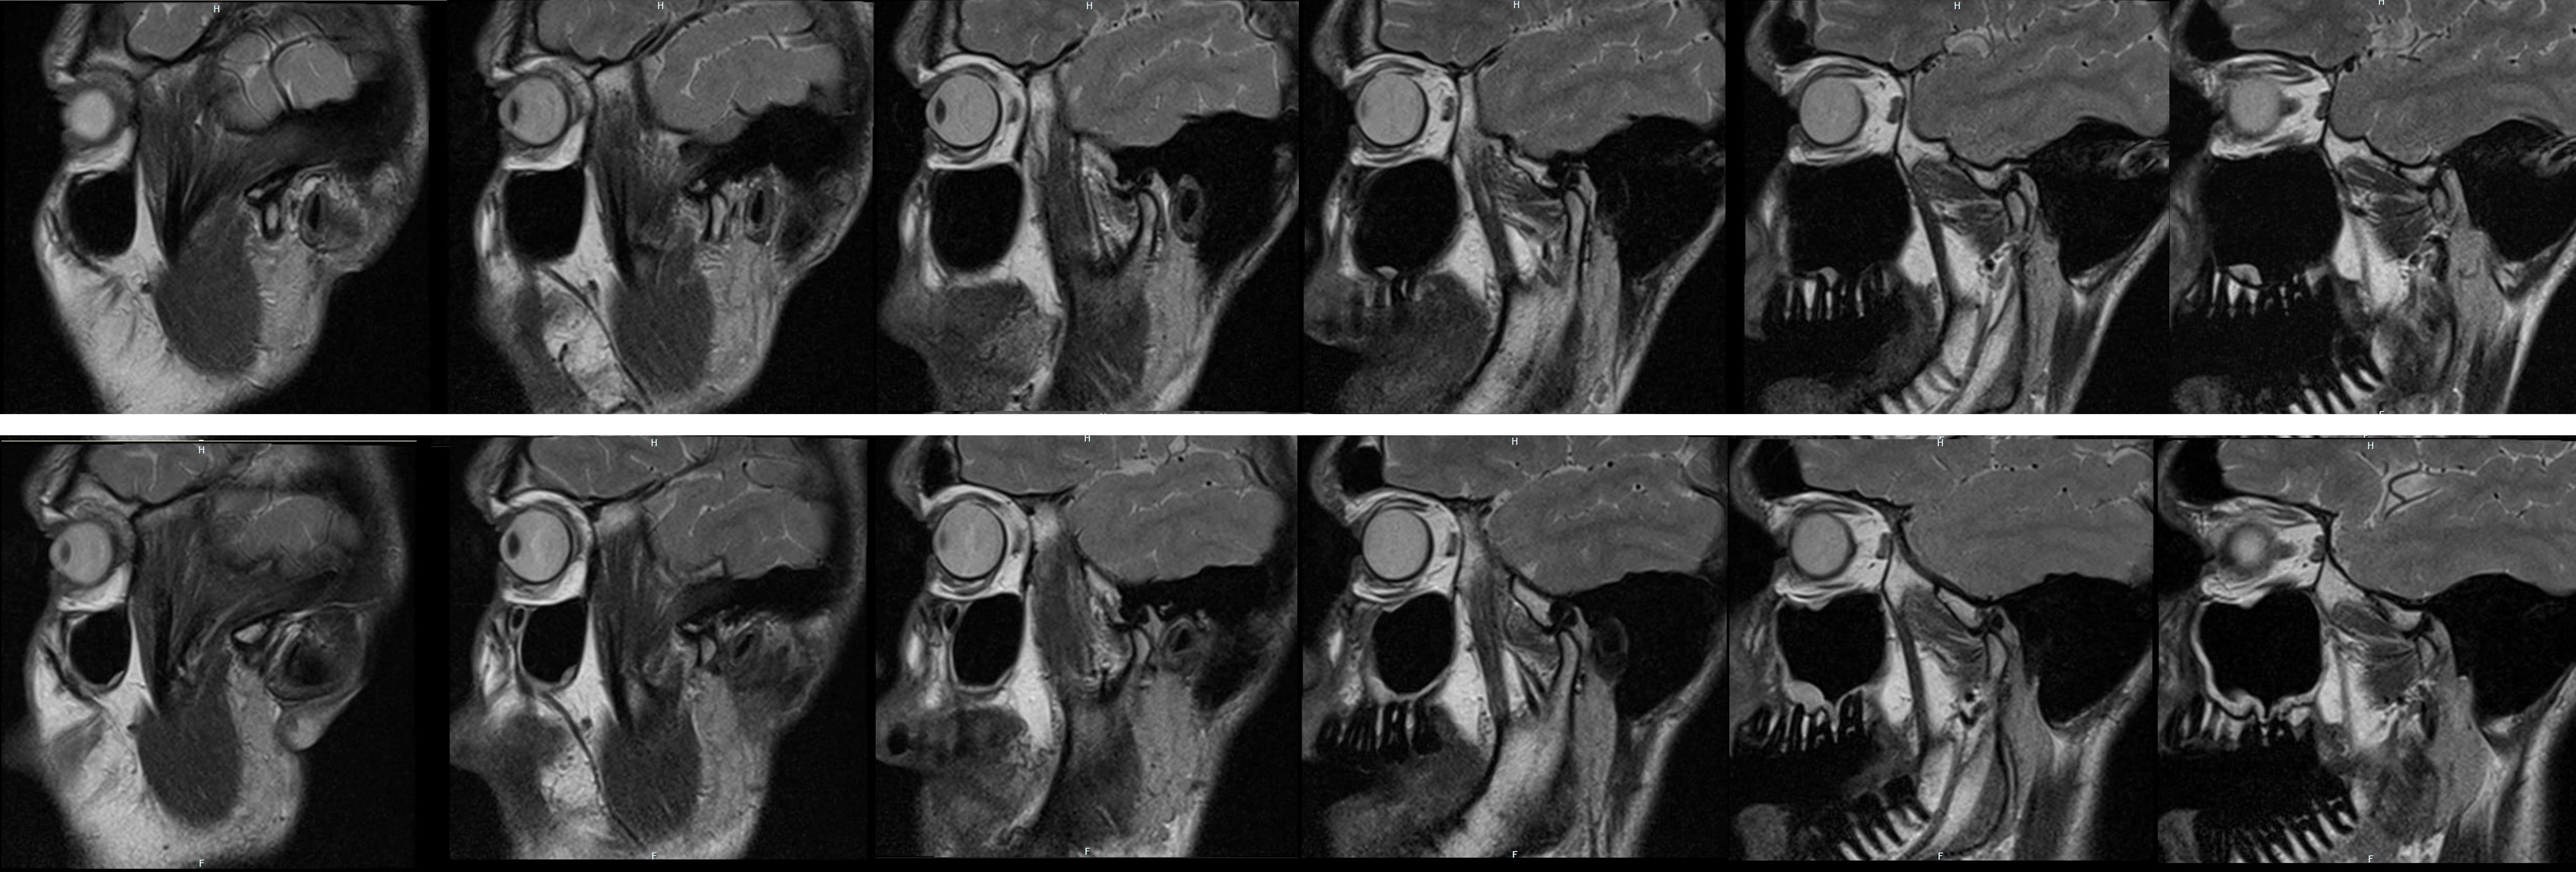

Пришло ревью моего МРТ челюхи. Я правильно понмаю что типа всё круто? А схуяли болит тогда? Я ещё попросил что-нить про горло написать, видимо чот у меня там подвоспалено в конце написали. (язык оригинала другой поэтому я в гугл переводчике скидываю сразу):

Заключение: Правильная конфигурация головки верхней челюсти в нормально выраженной впадине. Ровные и четкие границы суставных поверхностей с нормальной шириной кортикальной кости. Нормальный сигнал костного мозга.

Капюшонообразная конфигурация диска на корональных снимках, а также гантелеобразная конфигурация на угловых сагиттальных снимках.

Конфигурация на угловых сагиттальных снимках. При открывании рта диск регулярно следует за головкой нижней челюсти по суставному бугорку.

Отек слизистой оболочки у основания верхнечелюстной пазухи слева больше, чем справа. В остальном имеется регулярная пневматизация ННГ и сосцевидных отростков. Латеральная шпора носовой перегородки размером до 5 мм слева. Латерально симметричная орбита.

В области базальных ганглиев отсутствуют признаки пространственных зон отека.

Оценка: Регулярное сочленение височно-нижнечелюстных суставов с обеих сторон. Отсутствие вывиха фиброхряща и регулярные поступательные движения.

Вторичные признаки: отек слизистой оболочки у основания верхнечелюстной пазухи с обеих сторон и левая латеральная шпора носовой перегородки.